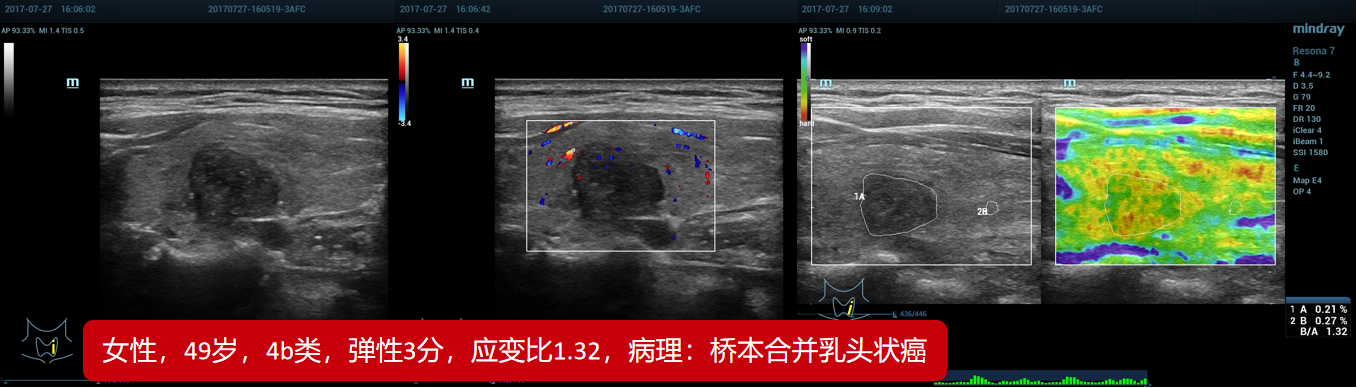

8、桥本合并乳头状癌(贵州医科大附属医院)

8、桥本合并乳头状癌(贵州医科大附属医院)